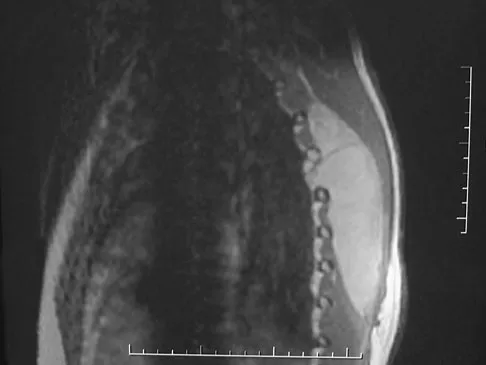

Figures 27a and 27b show the radiographs of a 32-year-old woman who was involved in a high-speed motor vehicle accident. She is neurologically intact. After stabilization and assessment, treatment should consist of

Explanation

The radiographs show a fracture-dislocation with translation in both the coronal and sagittal planes, evidence of significant instability requiring surgical stabilization. Anterior instrumentation is not as effective as posterior instrumentation in restoring stability, and because there is little bony destruction, the anterior column can be successfully reconstructed with simple realignment. The treatment of choice is multisegment posterior fusion with instrumentation. Lewandrowski KU, McLain RF: Thoracolumbar fractures: Evaluation, classification, and treatment, in Frymoyer JW, Wiesel SW (eds): The Adult and Pediatric Spine. Philadelphia, PA, Lippincott Williams and Wilkins, 2004, pp 817-843.